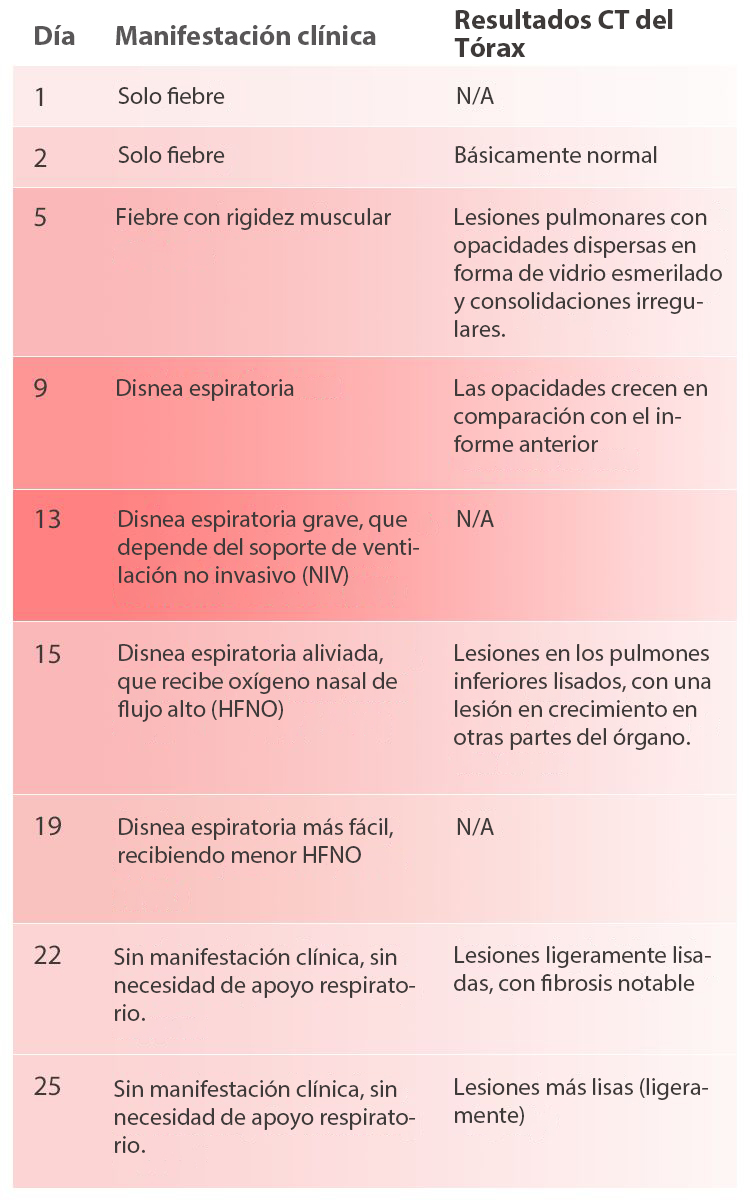

El paciente monitorizado en el estudio tenĂa antecedentes de contacto cercano con personas de Wuhan. El paciente registrĂł fiebre baja 5 dĂas antes del ingreso sin otros sĂntomas, y los resultados de CBC y CRP fueron normales. El nuevo examen al dĂa siguiente mostrĂł una ligera disminuciĂłn de WBC y un ligero aumento del valor de CRP. Las tabletas de levofloxacina se tomaron por vĂa oral siguiendo las instrucciones del mĂ©dico para el tratamiento antiinfeccioso. El dĂa de la admisiĂłn, el paciente tenĂa fiebre alta (mĂĄximo 39 â). La tomografĂa computarizada del tĂłrax mostrĂł lesiones pulmonares con opacidades dispersas y consolidaciones irregulares. El paciente recibiĂł un diagnĂłstico presuntivo como caso sospechoso de COVID-19.

Durante todo el proceso de diagnĂłstico y tratamiento, se han registrado las manifestaciones clĂnicas del paciente y los resultados de la tomografĂa computarizada del tĂłrax (ver Tabla 1), y tambiĂ©n los resultados de CBC y CRP (ver Figura 1).

El paciente en este caso tuvo fiebre como primer sĂntoma, con antecedentes epidemiolĂłgicos claros (contacto cercano con otra persona que regresa de Wuhan). La tomografĂa computarizada del tĂłrax antes del ingreso sugiriĂł que probablemente se trataba de un paciente con neumonĂa viral que luego se confirmĂł como un paciente COVID-19 despuĂ©s de la prueba de diagnĂłstico in vitro de ĂĄcido nucleico. DespuĂ©s del ingreso, la respiraciĂłn del paciente empeorĂł gradualmente a insuficiencia respiratoria. DespuĂ©s de la ventilaciĂłn mecĂĄnica y otros tratamientos relacionados, los sĂntomas clĂnicos bĂĄsicamente desaparecieron con mejores resultados de imĂĄgenes. El paciente fue dado de alta despuĂ©s de dos resultados negativos de la prueba de ĂĄcido nucleico.

A medida que la salud del paciente se deteriorĂł, el recuento de glĂłbulos blancos (WBC #) y el recuento de neutrĂłfilos (Neu #) aumentaron bruscamente despuĂ©s de una ligera disminuciĂłn, mientras que el recuento de linfocitos (Lym #) continuĂł disminuyendo. La relaciĂłn de neutrĂłfilos a linfocitos (NLR) aumentĂł rĂĄpidamente mientras que el valor de la PCR aumenta. En el momento mĂĄs crĂtico (el dĂa 13 despuĂ©s del inicio de los sĂntomas), WBC #, Neu #, NLR y CRP alcanzaron sus picos respectivamente, con Lym # en el punto mĂĄs bajo.

DespuĂ©s de un tratamiento mĂ©dico y cuidados adecuados, el paciente se recuperĂł gradualmente, con una rĂĄpida disminuciĂłn de WBC #, Neu #, NLR y CRP. En contraste, Lym # aumentĂł gradualmente. El dĂa 25, WBC #, Neu #, NLR, Lym # y CRP volvieron al rango normal. Aunque la tomografĂa computarizada mostrĂł que las lesiones en los pulmones aĂșn no habĂan desaparecido por completo, el paciente ya podĂa moverse sin oxigenoterapia. Lo mĂĄs importante, el resultado de la prueba de ĂĄcido nucleico se volviĂł negativo.